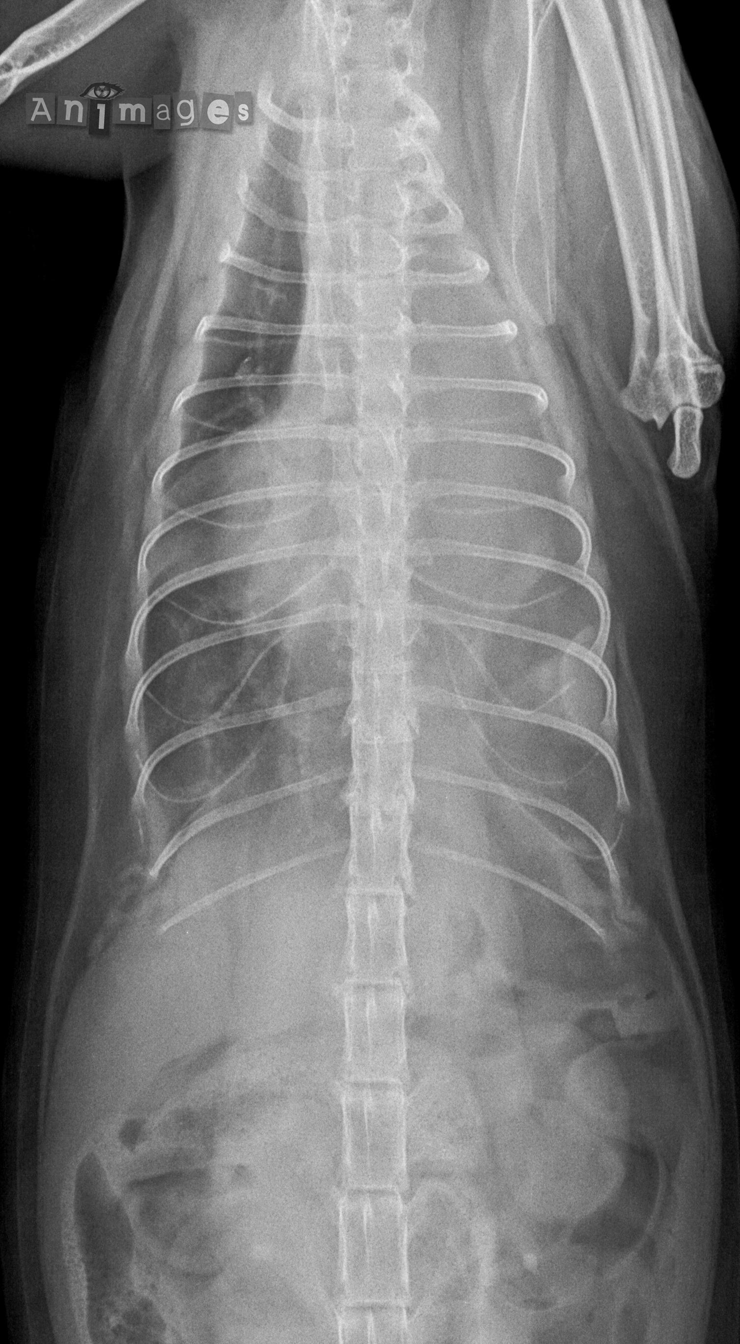

Ventrodorsale